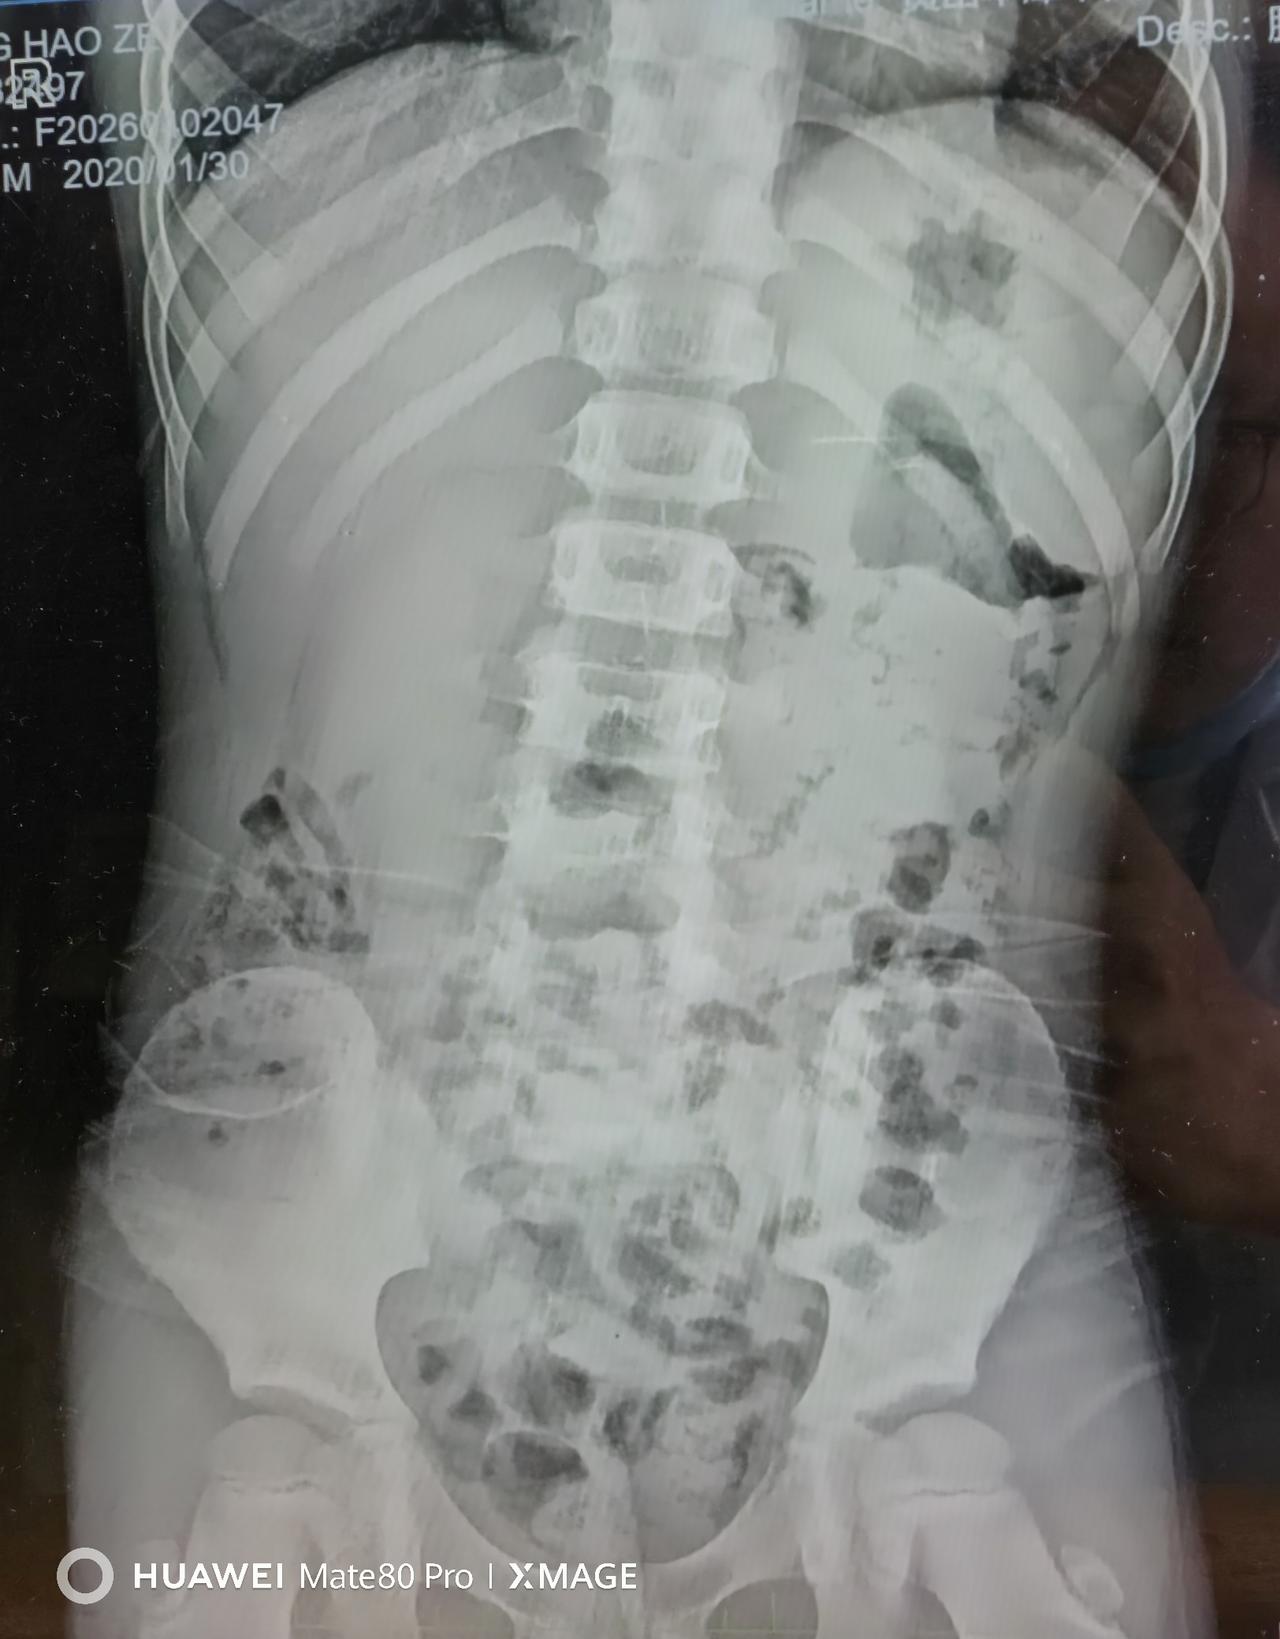

最近接诊了一个6岁小男孩,腹痛2天,还上吐下泻,当地医院拍了腹部立位片,看到明显的肠管扩张和气液平,直接诊断“肠梗阻”,建议紧急转上级医院。

家长抱着孩子一路狂奔过来,我们先给孩子查了血气,结果提示代谢性酸中毒+脱水,立刻给孩子补液、纠正酸中毒。神奇的是,仅仅1天,孩子腹痛、呕吐就明显缓解了,复查腹部立位片,之前的气液平、肠扩张竟然完全消失了!

气体、内容物堆积:肠道不蠕动,气体和粪便排不出去,肠管扩张、积气积液,拍片就会出现典型的“气液平、肠袢扩张”,和真性肠梗阻影像几乎无法区分。